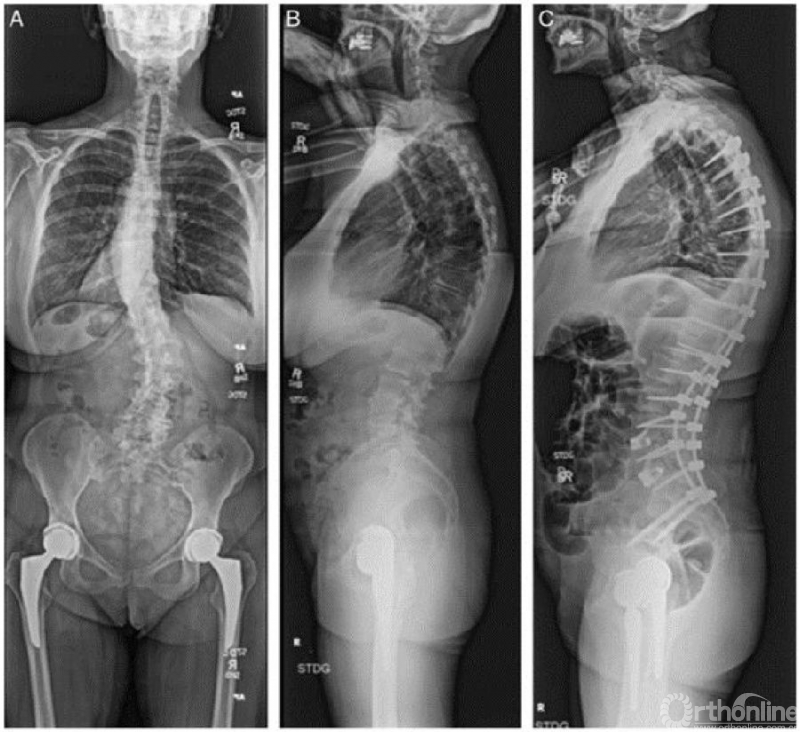

临床病例

63岁女性,患有症状性退变性脊柱侧凸,术前通过DXA检查、椎体骨折评估(VFA)和机会性CT检查进行综合评估(图3)。桡骨远端T值为-2.5,L1节段CT HU为71。25(OH)-维生素D水平为13。患者术前接受了9个月的特立帕肽治疗,并补充钙剂和维生素D。复查CT显示L1节段HU值提高至110。25(OH)-维生素D提升至32。随后患者接受了T4-骨盆固定融合术。术后继续使用特立帕肽治疗1年,没有发生骨质疏松相关并发症。

图3. A,术前脊柱全长正位片;B,术前脊柱全长侧位片;C,T4-骨盆固定融合术后1年脊柱全长侧位片,没有骨质疏松相关性并发症